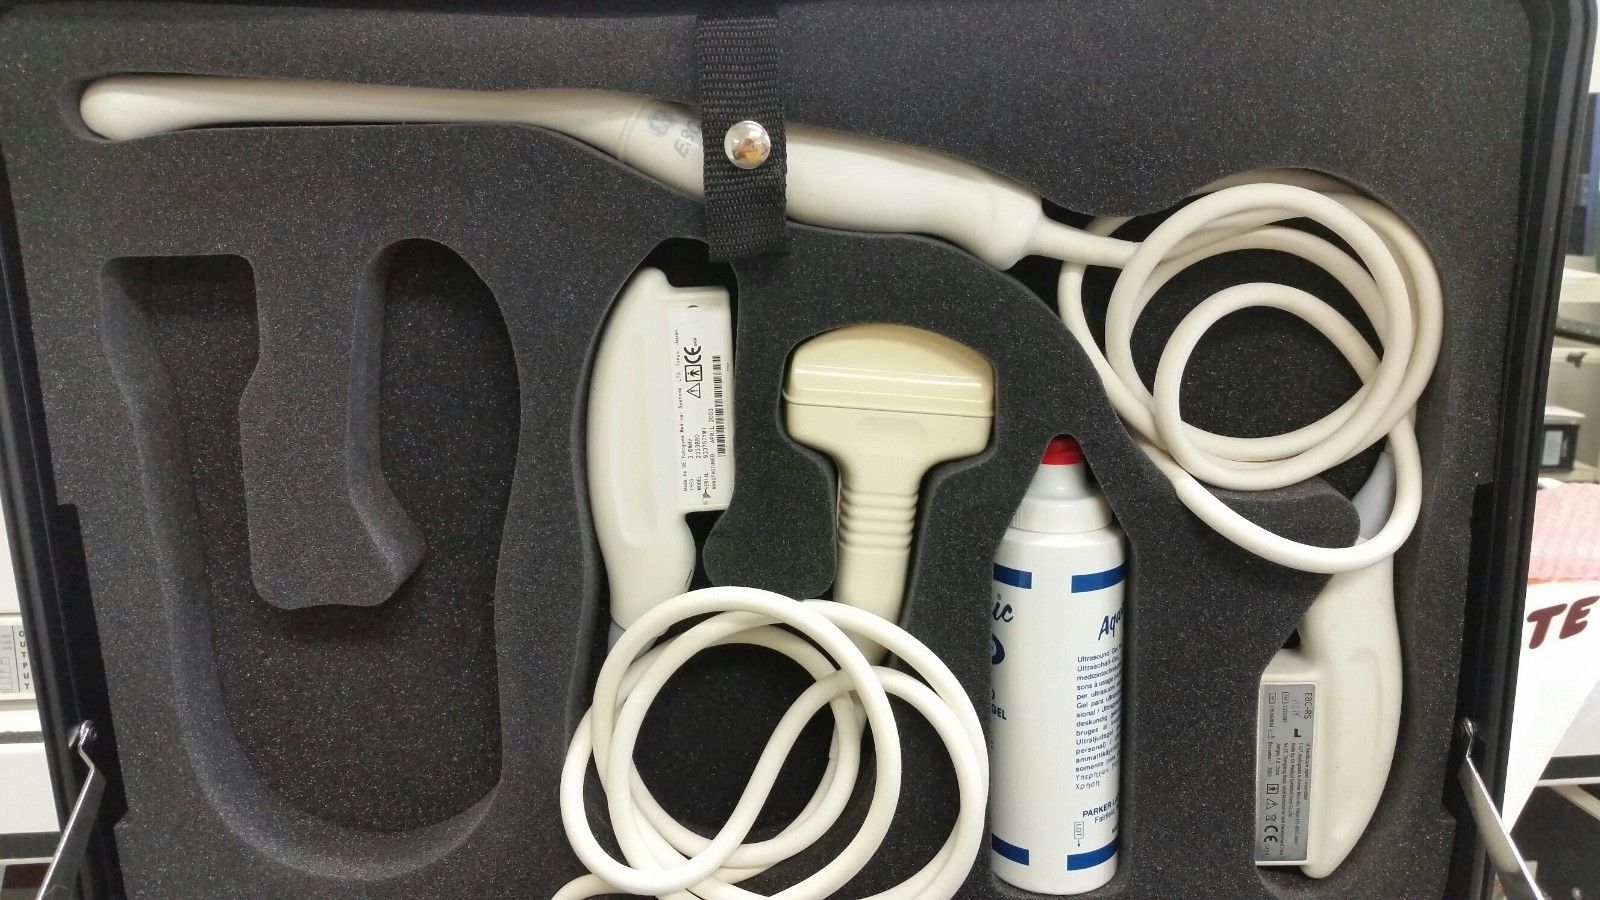

Explore the dependable and sophisticated GE Portable Logiq Book Ultrasound equipped with E8C-RS OB/GYN and 3C-RS Abdominal Transducers. Condition: Gently used with signs of cosmetic wear, yet remains fully operational for accurate diagnostics. Ideal for medical professionals seeking precision with a well-maintained machine. Brand: GE, Model: LOGIQ BOOK. Click to view our detailed listing and invest in advanced medical technology.